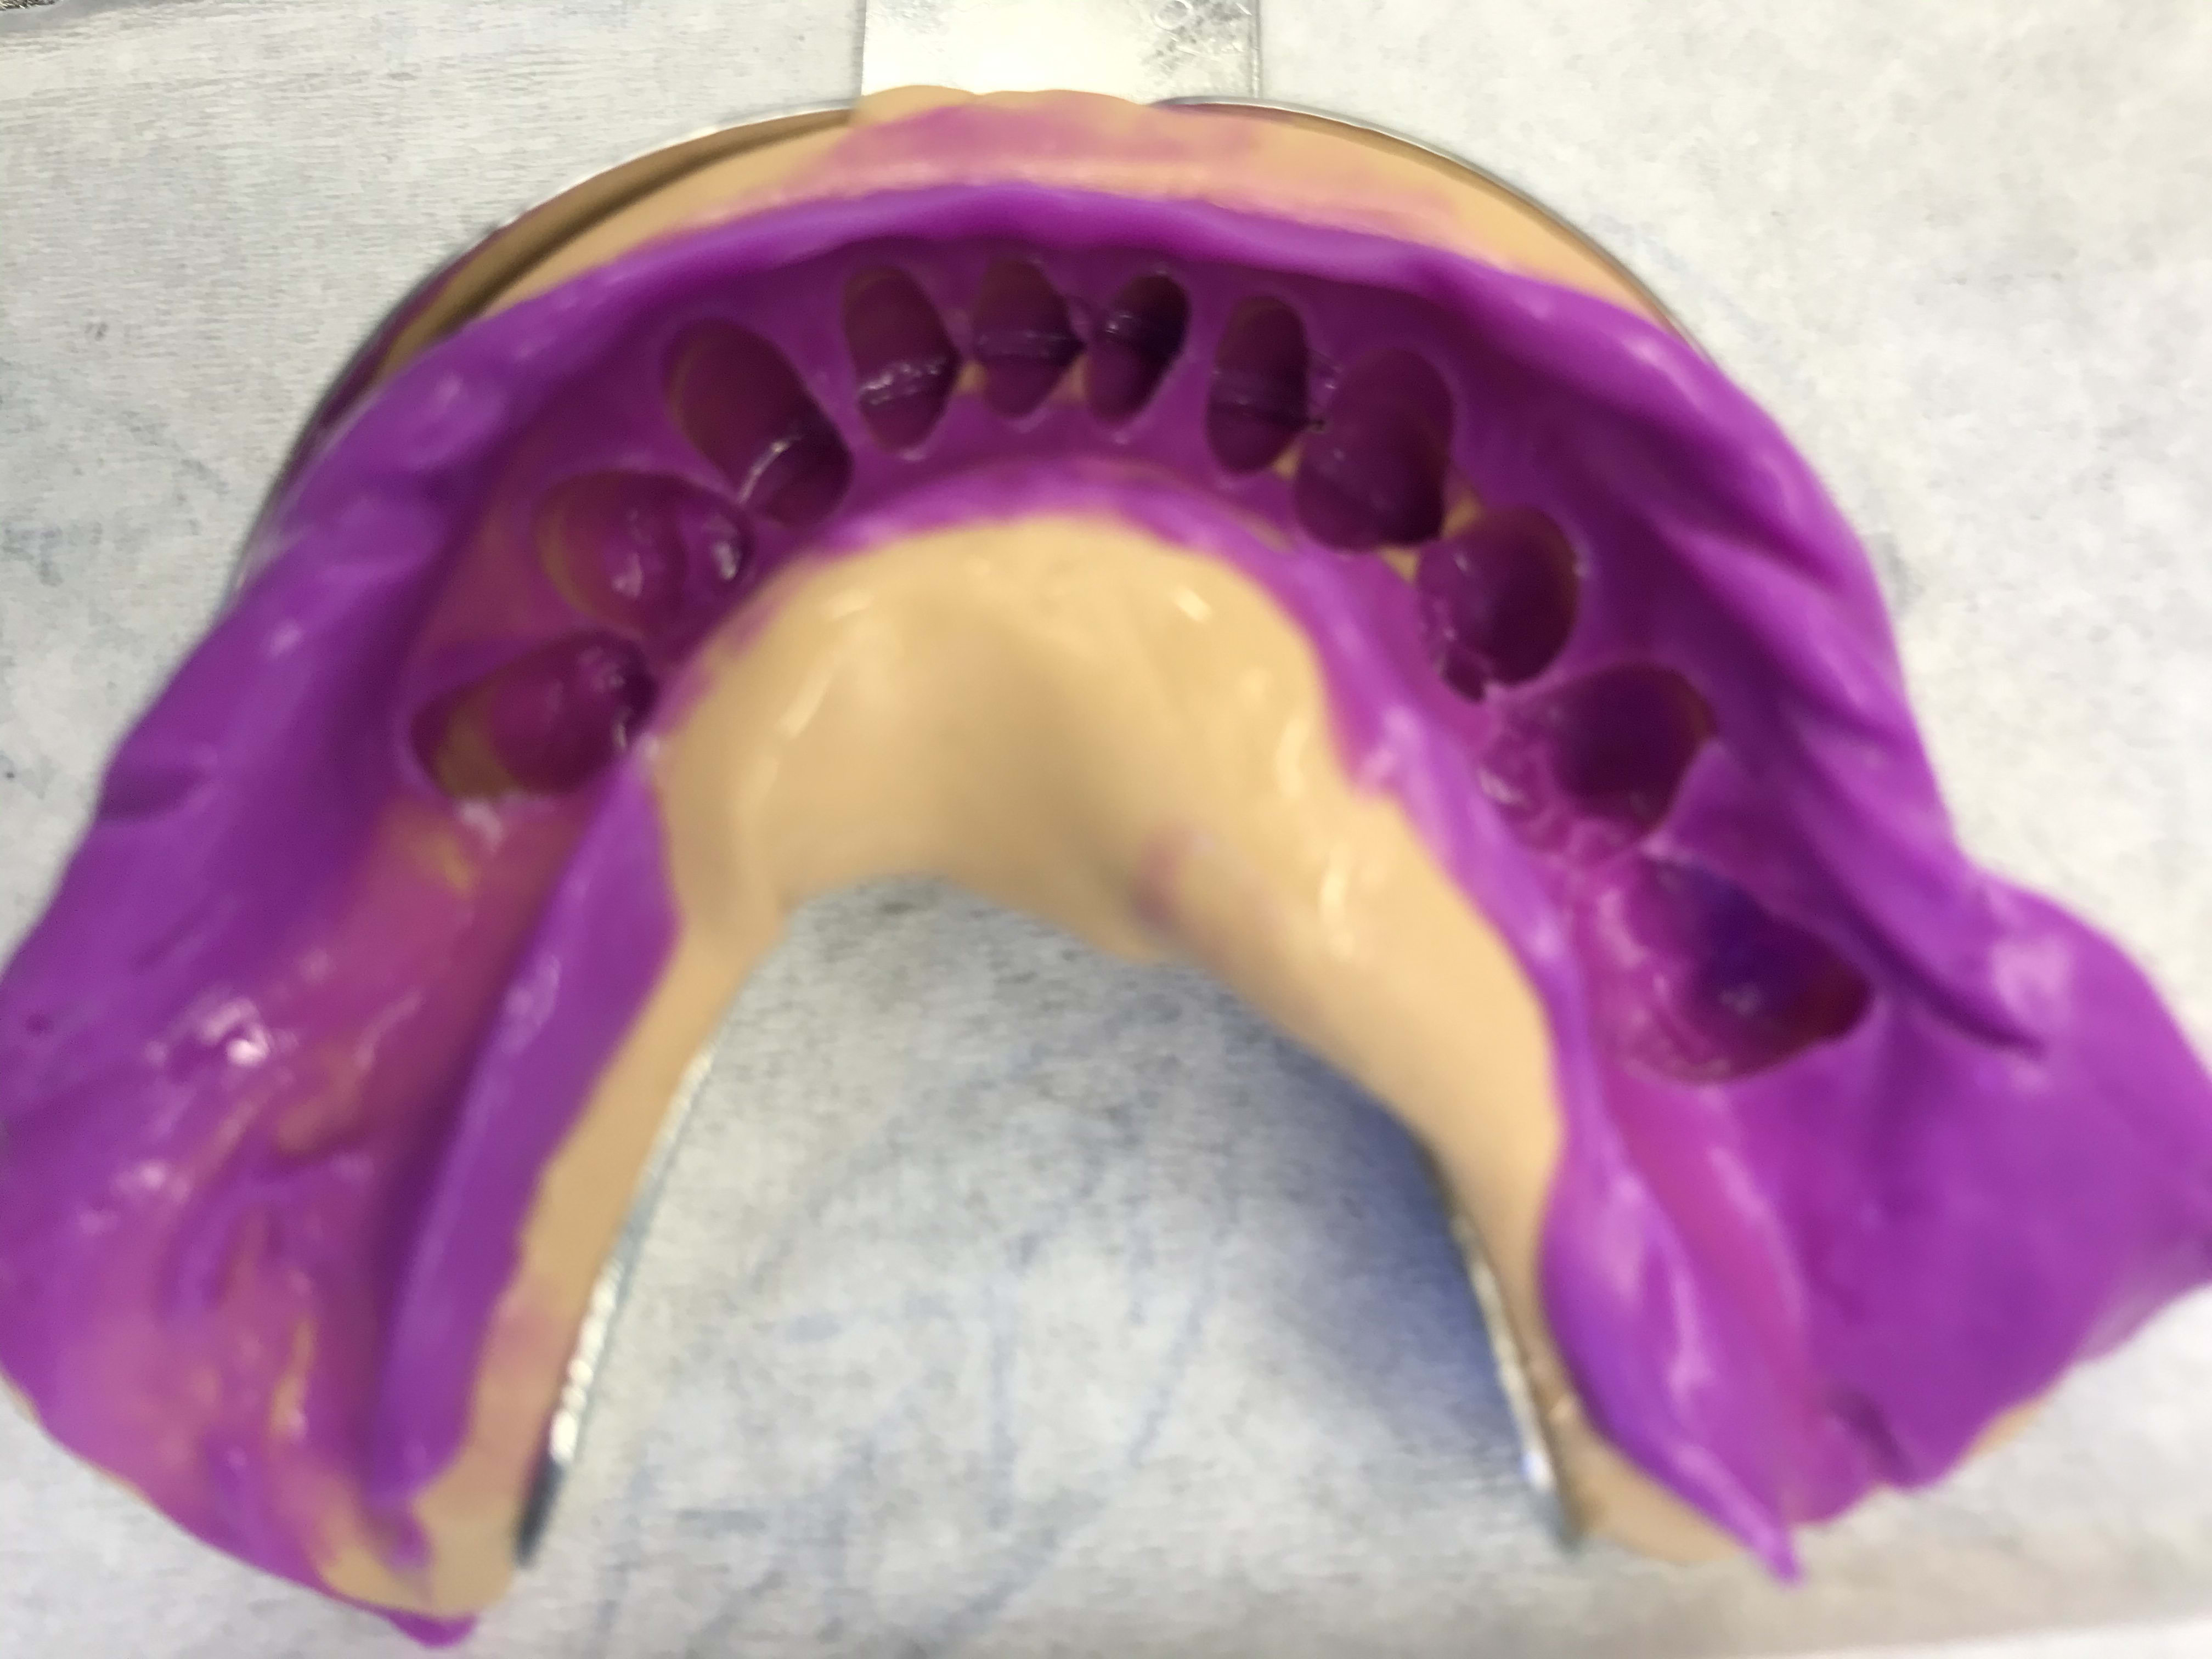

Il est toujours là gai-luron ? Voici la junior technique dont on avait parlé , c’est à dire la wash technique sans avoir besoin d’évider ton empreinte ou de mettre un film plastique ou autre .

1) du lourd. J’enlève mon PE, je remets mon PE en bouche, j’enlève je remets etc etc => les zones de manque correspondent au zones qui vont permettre de remettre le PE sans évider

2) du light

--

La forme de ma coupe de cheveux futuriste me permet une meilleure pénétration dans l'air et d' avoir moins de résistance face au vent lorsque je me déplace.